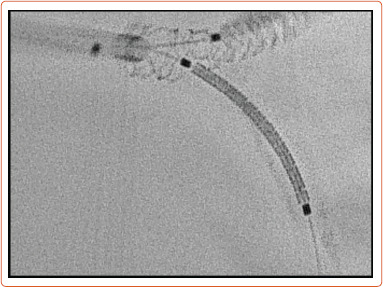

Abstract Image